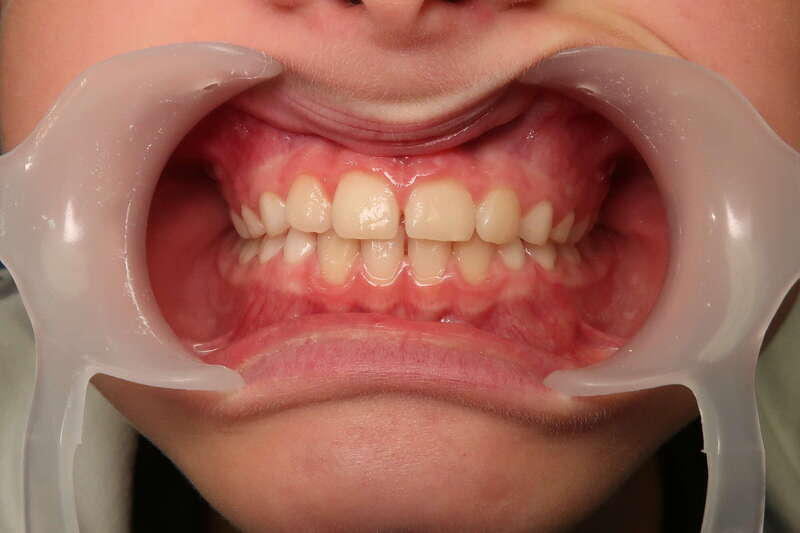

Cas n°1 traité par aligneurs (interception) - enfant

Ce cas d’interception chez un enfant de 8 ans démontre l'efficacité des aligneurs pour corriger des troubles fonctionnels précoces. Le diagnostic présentait des inversions d'articulé provoquant une déviation de la mandibule vers la gauche et un décalage des milieux.

Grâce à une coopération exemplaire et un traitement totalement indolore, l'expansion de l'arcade a permis de recentrer la mâchoire. Cette intervention a littéralement remis la croissance sur les rails, neutralisant le risque d'asymétrie faciale squelettique.

• Correction fonctionnelle : Recentrage immédiat de la mandibule et des milieux inter-incisifs.

• Prévention : Création d'un environnement favorable pour les dents définitives à venir.